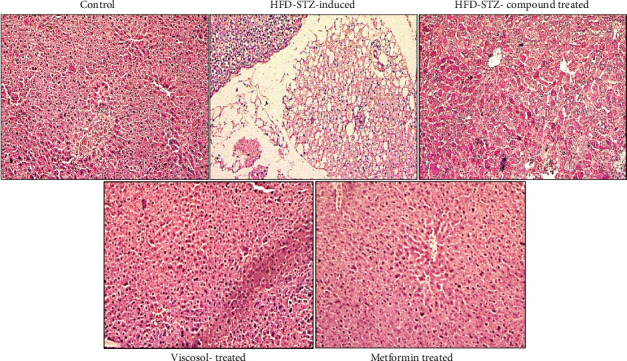

2型糖尿病(T2DM)是一种代谢紊乱,具有持续性高血糖、胰岛素抵抗和血脂异常的特征。蛋白酪氨酸磷酸酶1B (PTP1B)在T2DM患者的许多组织中被发现过表达,并参与胰岛素信号的负性调节。因此,抑制PTP1B可作为T2DM的治疗靶点。大量的研究表明,杜鹃具有抗炎、降血糖、保肝和降血脂的作用。在此之前,我们建立了高脂肪饮食(HFD)-低剂量链脲佐菌素(STZ)诱导的糖尿病雄性小鼠模型,并使用从粘家兔中分离的PTP1B抑制剂(5,7 -二羟基- 3,6 -二甲氧基-2-(4-甲氧基-3-(3-甲基-2-烯基)苯基)- 4h - chromen4 -one)治疗。在本研究中,我们旨在研究hfd - stz诱导的糖尿病小鼠模型脂肪和肝脏组织中PTP1B抑制的新生脂肪生成、脂肪细胞分化、脂蛋白清除增强、脂肪酸摄取、抗脂解活性和肝脏脂肪变性。我们发现化合物治疗组的脂肪细胞和肝细胞形态恢复正常。生化指标显示,化合物处理组血清LDL、VLDL、TC、TG逐渐降低。为了进一步验证我们的假设,我们进行了实时PCR,数据显示两种组织中PTP1B和其他炎症标志物的减少,胰岛素信号标志物(INSR, IRS1, IRS2和PI3K)的表达增强。我们的化合物上调脂肪细胞中的脂肪生成(PPARγ)、脂肪生成(SREBP1c、FAS、ACC和DGAT2)、脂蛋白清除(LPL、LDLR和VLDLR)、脂肪酸摄取(CD36和FATP1)和脂滴形成(FSP27和perilipin-1)标志物的表达,并下调肝细胞中的脂滴形成(FSP27和perilipin-1)标志物的表达。此外,我们发现胆固醇外排(在脂肪和肝脏)升高,脂肪细胞的脂解减少,肝细胞的脂解升高。因此,我们可以得出结论,我们的化合物保护脂肪细胞免受突然的脂肪分解和刺激脂肪细胞分化。此外,它还通过将脂蛋白和脂肪酸的清除和摄取转移到外周组织,恢复脂肪肝状况,发挥肝脏保护作用。

Type 2 diabetes mellitus (T2DM), a metabolic disorder, has the hallmarks of persistent hyperglycemia, insulin resistance, and dyslipidemia. Protein-tyrosine phosphatase 1B (PTP1B) was found to be overexpressed in many tissues in the case of T2DM and involved in the negative regulation of insulin signaling. So, PTP1B inhibition can act as a therapeutic target for T2DM. Numerous studies claimed the anti-inflammatory, hypoglycemic, hepatoprotective, and hypolipidemic activities of Dodonaea viscosa. Previously, we generated the high-fat diet (HFD)-low dose streptozotocin (STZ)-induced diabetic male mice model and treated it with a PTP1B inhibitor (5, 7-dihydroxy-3, 6-dimethoxy-2- (4-methoxy-3- (3-methyl-2-enyl) phenyl)-4H-chromen-4-one), isolated from Dodonaea viscosa. In the current study, we aimed to investigate the De novo lipogenesis, adipocyte differentiation, augmentation of lipoproteins clearance, fatty acid uptake, antilipolysis activity, and hepatic steatosis of PTP1B inhibition in adipose and liver tissues of the HFD-STZ-induced diabetic mice model. We found the retrieval of normal morphology of adipocytes and hepatocytes in the compound-treated group. The biochemical parameters showed the gradual reduction of LDL, VLDL, TC, and TG in the serum of the compound-treated group. To further test our hypothesis, real-time PCR was performed, and data revealed the reduction of PTP1B and other inflammatory markers in both tissues, showing enhanced expression of insulin signaling markers (INSR, IRS1, IRS2, and PI3K). Our compound upregulated the adipogenic (PPARγ), lipogenic (SREBP1c, FAS, ACC, and DGAT2), lipoprotein clearance (LPL, LDLR, and VLDLR), fatty acid uptake (CD36 and FATP1), and lipid droplet forming (FSP27 and perilipin-1) markers expressions in adipocytes and downregulated in hepatocytes. Furthermore, we found elevated cholesterol efflux (in adipose and liver) and decreased lipolysis in adipocytes and elevated in hepatocytes. Hence, we can conclude that our compound protects the adipocytes from abrupt lipolysis and stimulates adipocyte differentiation. In addition, it plays a hepatic protective role by shifting clearance and uptake of lipoproteins and fatty acids to the peripheral tissues and retrieving the fatty liver condition.